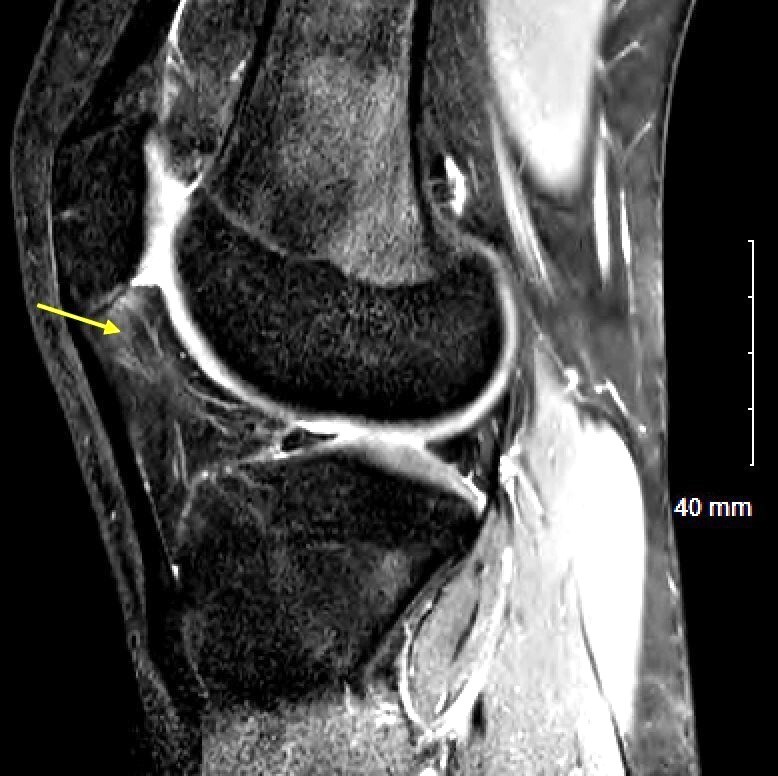

On physical exam he had no pain with patellar grind test but had pronounced pain to palpation of the infrapatellar fat pad. He had painless range of motion of 0-130 degrees and had no J sign and did not demonstrate patellar maltracking. Ligamentous exam was stable and neurovascular exam was intact. His MRI demonstrated hypertrophy and swelling of the infrapatellar fat pad (Figure 3). Given his history and imaging findings a diagnostic fat pad injection was chosen as the initial course of treatment. Following injection, the patient underwent treadmill running and noted a near complete resolution of symptoms and as such the decision was made to proceed with arthroscopic fat pad resection, starting with the more symptomatic right side.

Using the same technique described in Case 1,16 thick bands of fibrotic scar tissue were identified on the posterior surface of the markedly enlarged infrapatellar fat pad (Figure 4). Following resection of three-quarters of the fat pad, the arthroscope was then placed in the standard anterolateral portal to carry out further diagnostic exam.

In the first month post op, he noted resolution of his anterior knee pain and sought out a second arthroscopic fat pad resection on his contralateral knee. Eight weeks after his initial surgery, the left sided arthroscopic fat pad resection was performed, using the same technique. Again, he was found to have a markedly enlarged thickened and fibrotic fat pad. This was carefully resected, with the patellar tendon protected.